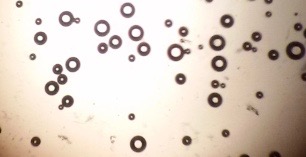

Morphological characterization using TEM

The morphology of niosomal dispersion was observed using transmission electron microscopy (JEM-2100, USA). A drop of dispersion was cleaned with phosphate buffer pH 7.4 and put on carbon-coated 300 mesh copper grid and left for 1 minute to form a thin film. These films were then negatively stained with 2% (w/v) phosphotungstic acid solution. After drying with air, the stained films were photographed using TEM [27]. The experiment was performed at room temperature, and micrographs were taken at suitable magnification power.

Vesicles formation was further confirmed by TEM. The transmission electron microscopy photographs of the niosomes prepared from proniosomal formulae are shown in fig. (29-56). From the presented figures, it is apparent that the majority of the vesicles are well identified, nanosized and separate with sharp outermost bilayer boundaries having large internal space. The vesicles seem to be like a spherical reservoir and devoid of any surface artifacts.